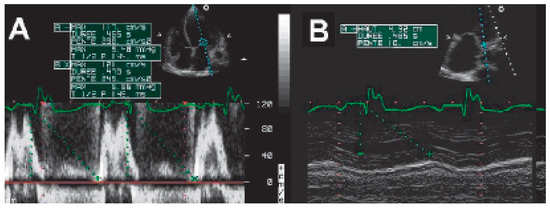

The incidence of heart failure is increasing and patients are threatened to die of pump failure as well as of sudden cardiac death (SCD). Lately, cardiac resynchronisation therapy (CRT) has been introduced to treat patients with persistent heart fail...